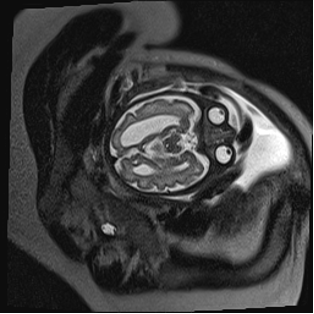

Fetal MRI was performed in three cases. It confirmed the ultrasound suspicion of ACC and revealed no additional anomalies. The remaining two corresponded to ventriculomegaly—one severe and one associated with dilation of the suprapineal recess—suggesting a possible but unconfirmed obstructive etiology (Figures 1-3).

Figure 3. Colpocephalic dilatation of the left ventricle and significant loss of white matter volume in the ipsilateral temporo-occipital region.

<b>Figure 3.</b> Colpocephalic dilatation of the left ventricle and significant loss of white matter volume in the ipsilateral temporo-occipital region.